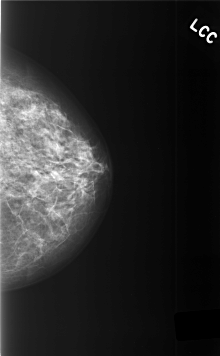

ics_version 1.0 filename C-0471-1 DATE_OF_STUDY 8 9 1997 PATIENT_AGE 48 FILM FILM_TYPE REGULAR DENSITY 2 DATE_DIGITIZED 28 12 1998 DIGITIZER LUMISYS LASER SEQUENCE LEFT_CC LINES 5696 PIXELS_PER_LINE 3520 BITS_PER_PIXEL 12 RESOLUTION 50 NON_OVERLAY LEFT_MLO LINES 5416 PIXELS_PER_LINE 4112 BITS_PER_PIXEL 12 RESOLUTION 50 NON_OVERLAY RIGHT_CC LINES 5768 PIXELS_PER_LINE 4056 BITS_PER_PIXEL 12 RESOLUTION 50 OVERLAY RIGHT_MLO LINES 5936 PIXELS_PER_LINE 4168 BITS_PER_PIXEL 12 RESOLUTION 50 OVERLAY |